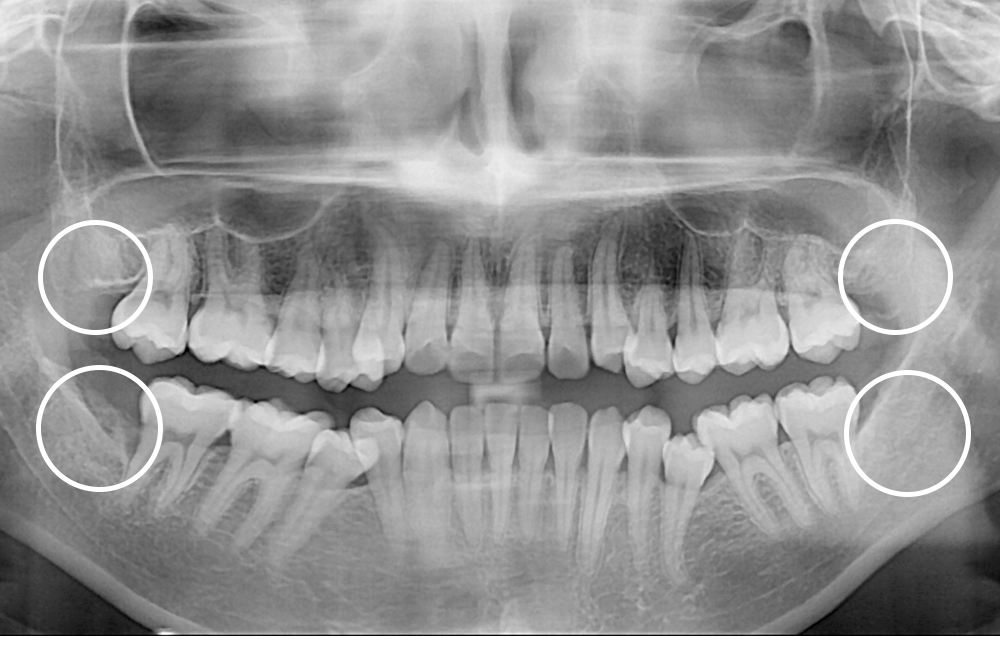

[사랑니] 매복 사랑니 발치

치료전 : 2020-05-20

세종치과는 구강악안면외과학 박사이신 원장님이 발치하는 치과입니다.